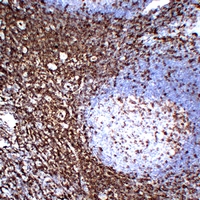

(Immunohistochemical analysis of CD43 staining in human anaplastic large cell lymphoma formalin fixed paraffin embedded tissue section. The section was pre-treated using heat mediated antigen retrieval with sodium citrate buffer (pH 6.0). The section was then incubated with the antibody at room temperature and detected using an HRP conjugated compact polymer system. DAB was used as the chromogen. The section was then counterstained with haematoxylin and mounted with DPX.)